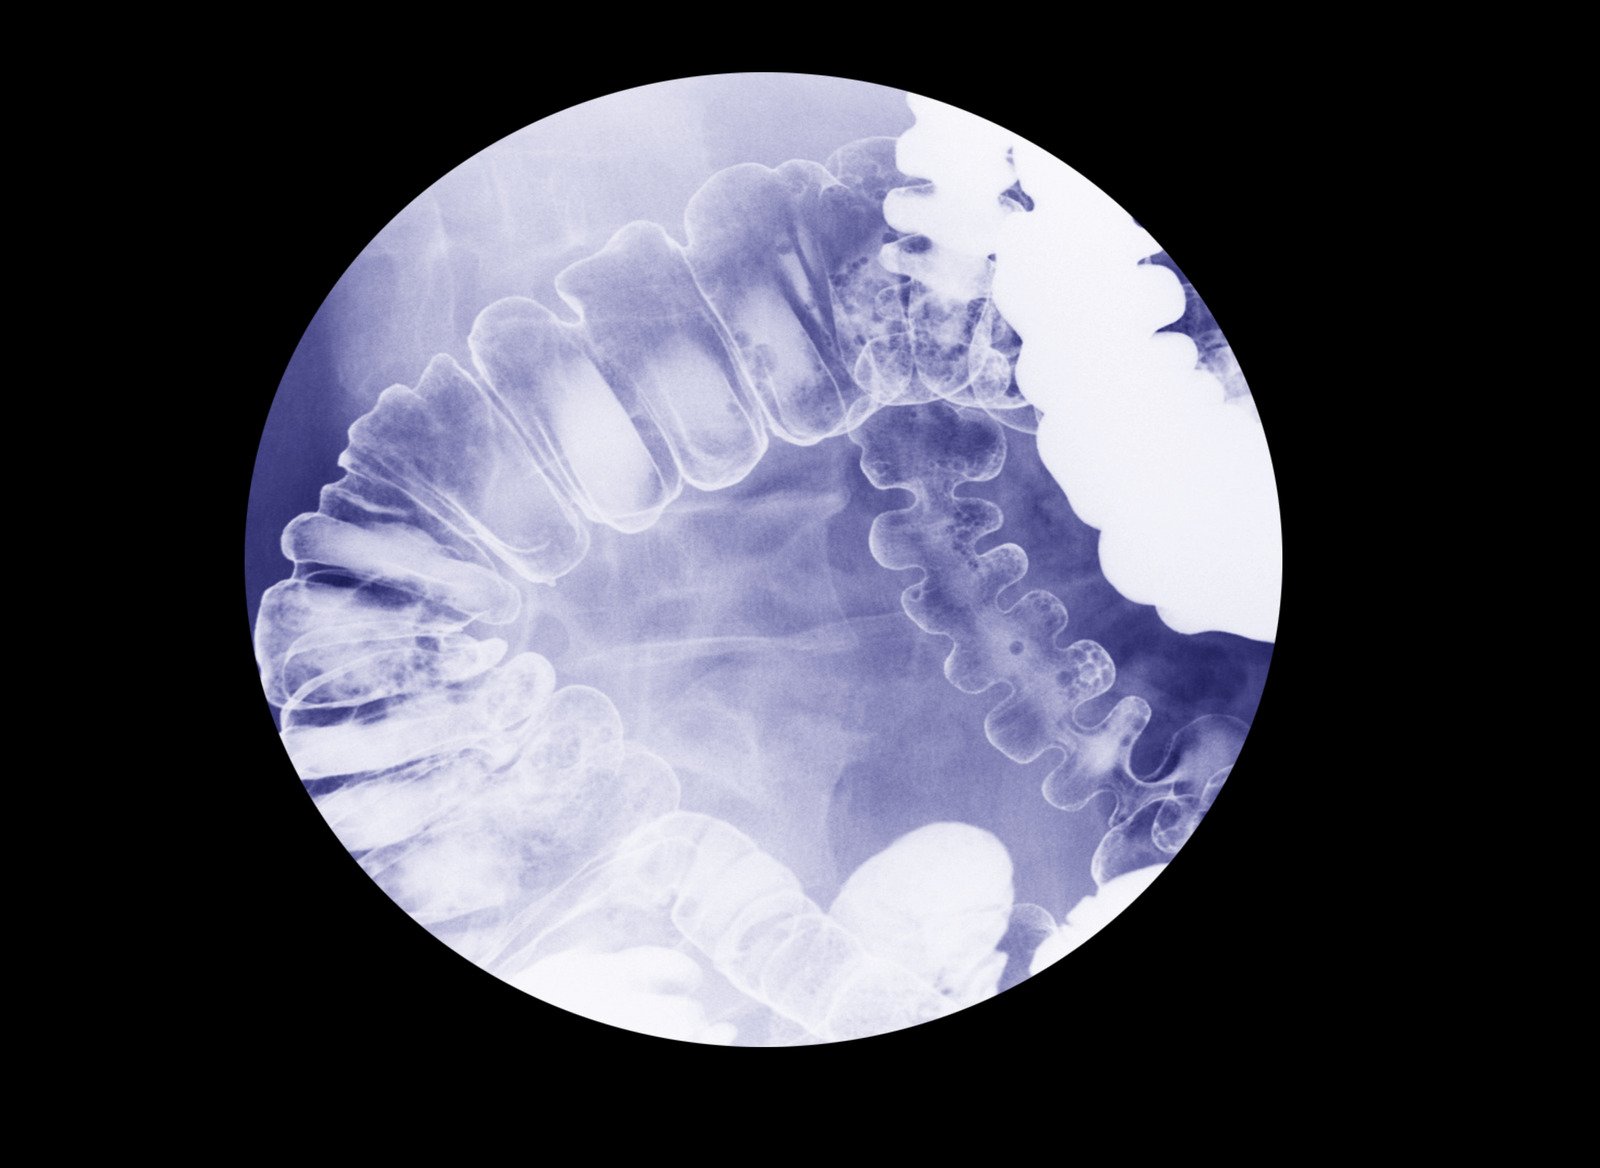

바륨 조영술: 식도와 위의 구조적 이상을 확인하는 X선 검사

바륨 조영술은 식도와 위의 구조적 이상을 진단하기 위해 바륨을 이용하여 X선 촬영을 하는 검사입니다.

바륨은 X선에서 뚜렷하게 보이는 성질이 있어 식도와 위의 내부 구조를 선명하게 보여줍니다.

바륨 조영술은 바륨 현탁액을 마신 후 X선을 촬영하여 식도, 위, 십이지장의 형태와 기능을 평가하는 검사입니다.

바륨은 밀도가 높아 X선에서 흰색으로 나타나므로 내부 장기의 윤곽과 이상 유무를 정확하게 파악할 수 있습니다.